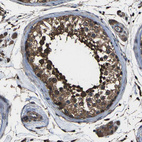

Immunohistochemical staining of human testis shows moderate to strong cytoplasmic positivity in cells in seminiferous ducts.